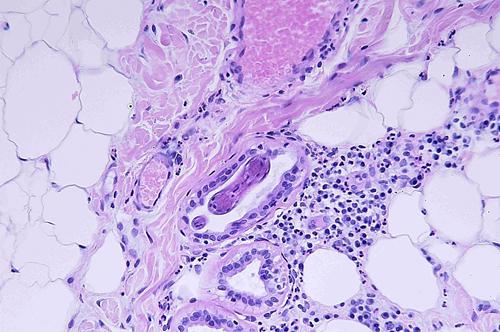

Photo 24 (Hémalun Eosine X200) peau velue : Certains éléments vermiformes

sont contenus dans la lumière des glandes sudorales apocrines

épitrichiales, ici un élément en coupe longitudinale tangentielle.

Légendes de la Photo 24 :

- Étoile rouge vides : vaisseaux sanguins (lumière de)

- Étoile rouge pleine : infiltrat inflammatoire dermique périsudoral

- Rond marron : collagène

- Étoiles turquoises : adipocytes

- Flèches juanes : glandes sudorales apocrines épitrichiales

- Flèche vertes : section d’un élément vermiforme rond